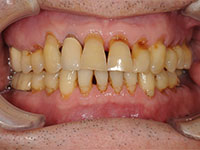

⑥咬耗

上下の歯を強い力でこすることにより歯が削れてしまっています。

⑦過蓋咬合

下の歯が全く見えないほど、上の歯が深く被さっています。噛み合わせが深いため奥歯でしか物を噛もうとしません。したがって奥歯で強く食いしばります。